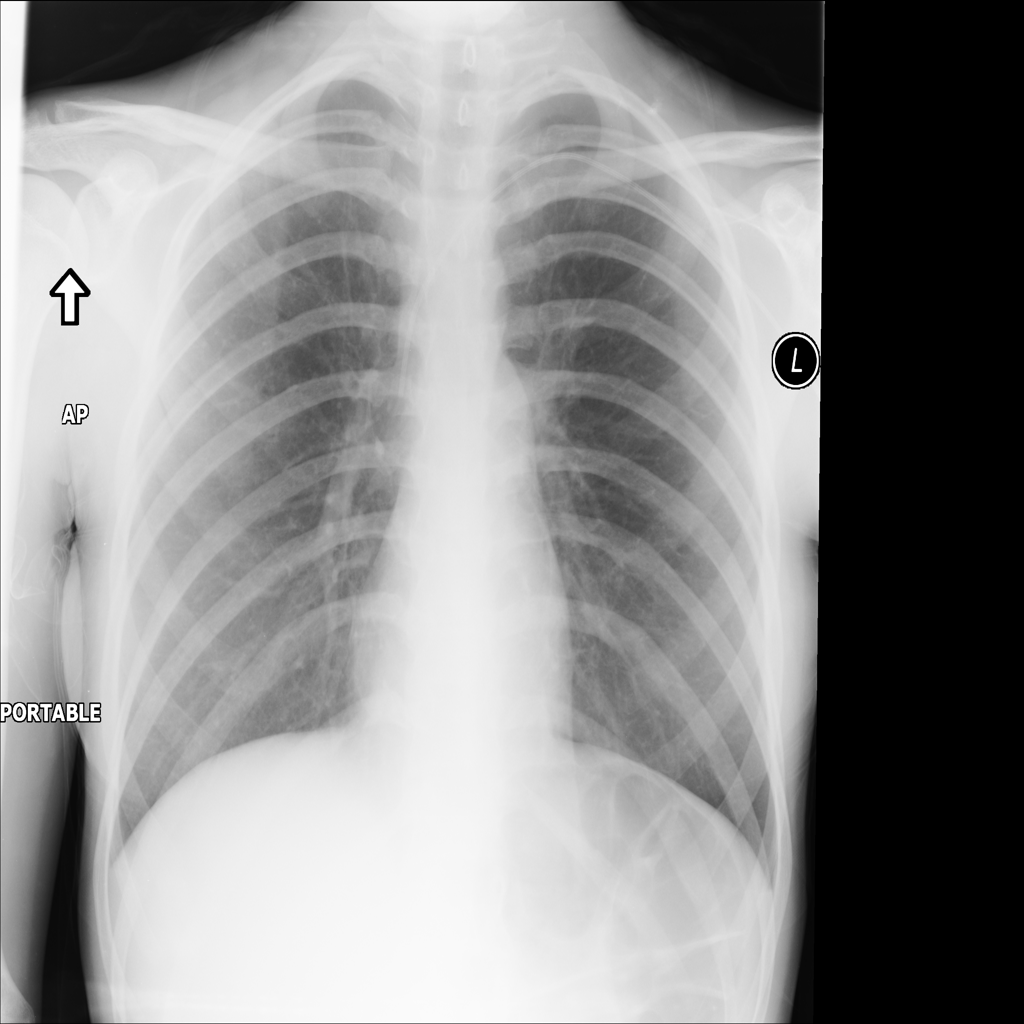

PAT-A1E2 · IMG-001Pneumonia

PAT-A1E2 · IMG-001

AP